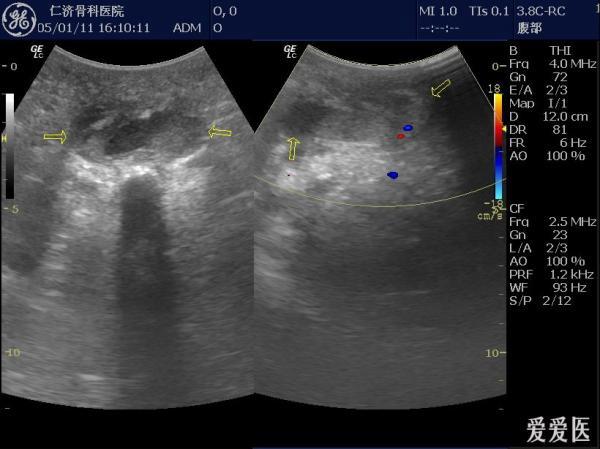

b超提示坐骨结节囊肿.

坐骨结节囊肿